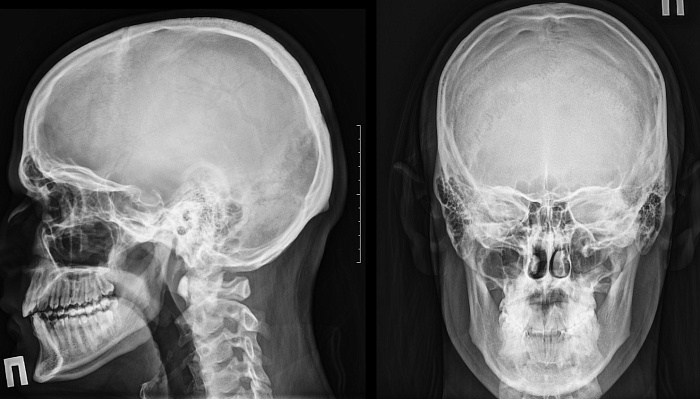

Рентгенография черепа – важный метод рентгенологического исследования состояния различных костных зон черепа.

1. Рентгенография черепа стандартная

Стандартное рентгенологическое исследование костей черепа в двух проекциях.